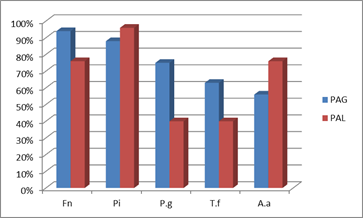

Los microorganismos que aparecieron con mayor prevalencia en los cuadros de Periodontitis Agresiva fueron P. intermedia y F. nucleatum. Éstos aparecieron en el 93% y 83% de los pacientes respectivamente. Le siguió en incidencia A. actinomycetemcomitans, microorganismo que se correlaciona fuertemente con los cuadros de Periodontitis Agresiva 9,11-12,16. A.actinomycetemcomitans apareció en el entorno del 70% de los pacientes estudiados (Graf. 1).

Cuando se hace la distinción entre Periodontitis Agresiva Localizada y Generalizada, la microbiota se diferencia poniendo en relieve la distinta etiopatogenia microbiológica de ambos cuadros. Cabe resaltar, que de los cuadros agresivos estudiados, el 60% de los casos correspondió a casos localizados y el 40% a cuadros generalizados. Es por este motivo que al estudiar la microbiota de los cuadros agresivos sin distinguir entre localizados y generalizados, los porcentajes de prevalencia están condicionados por el mayor número de casos localizados.

Si bien en ambos tipos de cuadros F. nucleatum fue un microorganismo de alta prevalencia, se destacó fundamentalmente en los cuadros agresivos generalizados presentándose en casi el 95% de los pacientes.

En los cuadros generalizados, el microorganismo que le siguió en prevalencia fue P. intermedia (en el entorno del 90%), seguido por P. gingivalis en el 75% de las muestras y por T. forsythia en un 63%. Por otra parte, A. actinomycetemcomitans si bien es recuperado en varios pacientes, fue de los microorganismos estudiados, el menos prevalente presentándose en un 56% (Graf. 2).

Periodontitis Agresiva Localizada

En cuanto al cuadro localizado el microorganismo más prevalente fue P. intermedia presentándose en el 96% de los pacientes, seguido de F. nucleatum y A. actinomycetemcomitans ambos con una prevalencia en el entorno del 75%. Se destaca la mayor prevalencia de A. actinomycetemcomitans que en los cuadros generalizados. Esto es concordante con la importancia que tiene este microorganismo en los cuadros localizados 13-15. Finalmente, los microorganismos P. gingivalis y T. forsyhtia presentaron la menor prevalencia detectándose en el 40% de los pacientes estudiados (Gráf. 3).

Comparativo de la prevalencia microbiana entre PAG y PAL

Para facilitar la comparación, a continuación se presenta en forma consolidada las respectivas prevalencias de los diferentes patógenos en los cuadros generalizados y localizados en nuestros estudios con pacientes uruguayos (Graf. 4).